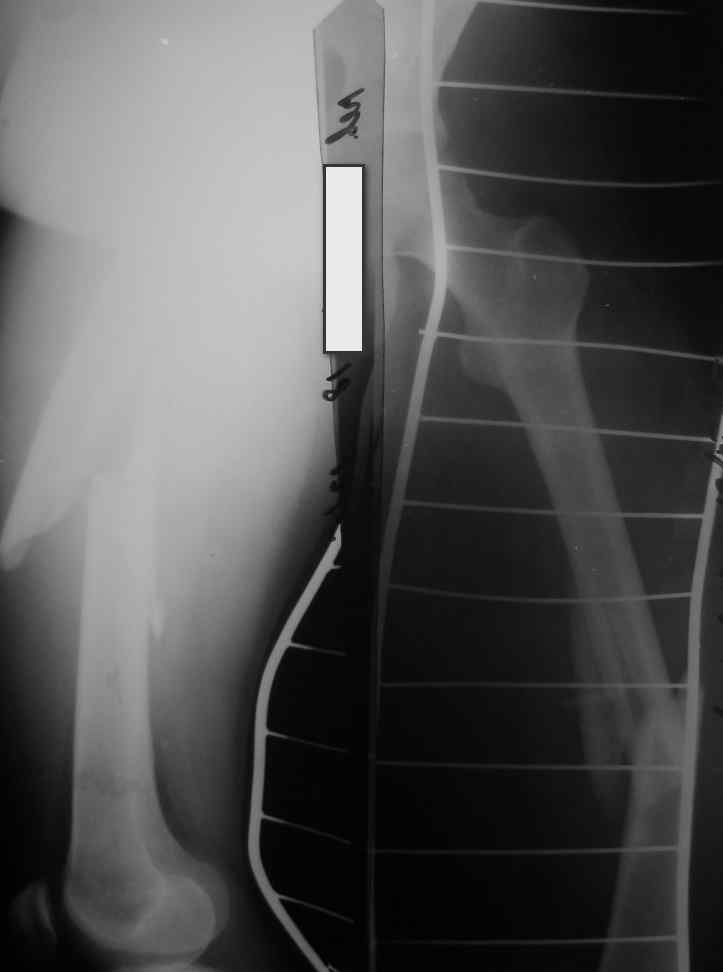

Поступила молодая,маленькая девочка 18 лет с болями в левом бедре. Из истории:автодорожная травма в ноябре 2005 года, тогда же оперировалась данным способом. Проживает в селе и как правило в таких случаях выпала из поля зрения ведущего доктора.

Ноябрь 2005г. и 18 лет это не 6-8мес это год. на последних снимках разве мы видим элементы "ЗДОРОВОЙ" консолидации сдесь должна быть серьезная гипертрофическая мазоль.